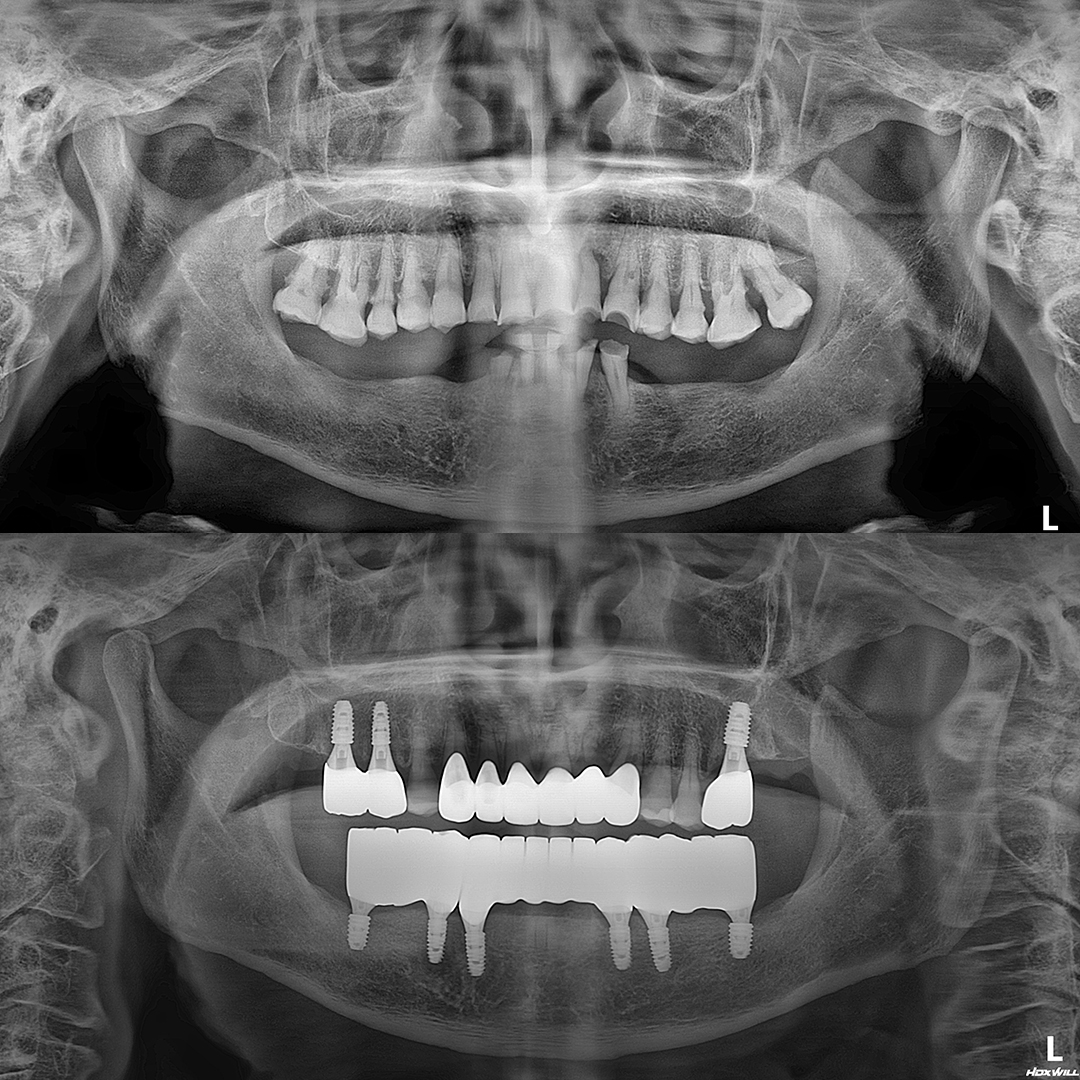

전체 임플란트

상·하악 전체 치아를 대체하는 임플란트로 최소한의 식립을 통해

자연치아와 비슷한 기능을 수행할 수 있도록 합니다.